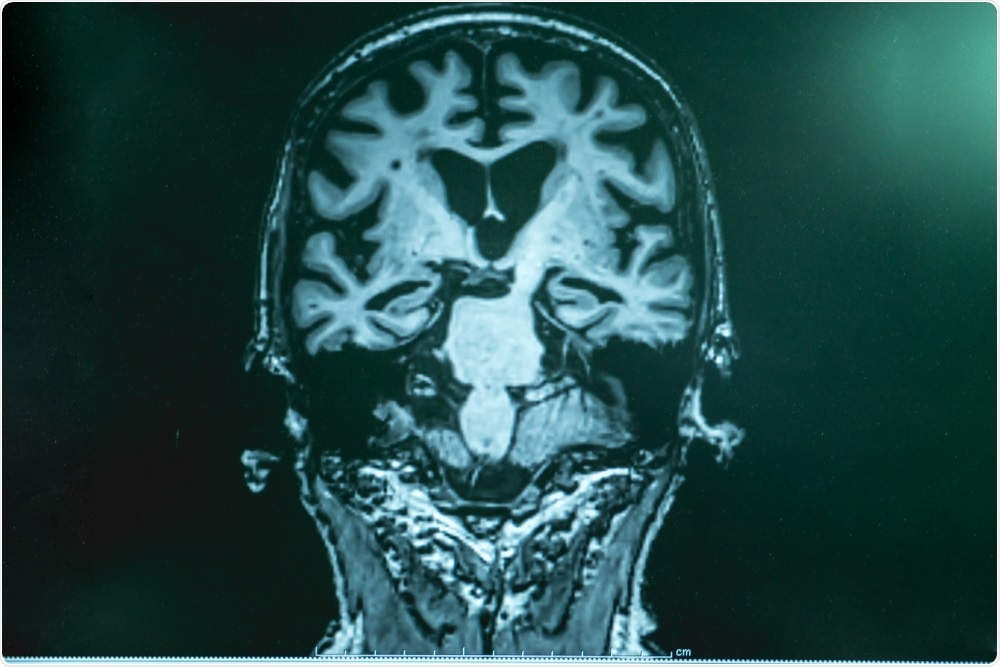

Neuroscientists

Image Credit: Gorodenkoff/Shutterstock.com